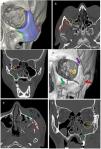

Frontal fracture. (A) Axial computed tomography (CT) with a bone window. Comminuted fracture of the anterior and posterior walls of the frontal sinus with occupation of the same and communication with the anterior cerebral fossa. (B) Axial CT with a brain window. Laminar subdural haematoma and bilateral frontobasal contusive foci.

(A) Representation of the five cardinal lines of the NOE region: nasal bone and piriform aperture (blue), medial maxillary buttress (yellow), floor of orbit (green), medial wall of orbit (purple) and frontomaxillary suture (red). (B and C) Axial computed tomography (CT) with a bone window and 3D reconstruction. Comminuted left NOE fracture with displaced and depressed fragments. Involvement of the nasolacrimal duct (arrow tip). Palpebral emphysema and blood in the sinus. (D and E) Axial CT with a bone window and 3D reconstruction. Left NOE fracture with large fragment without displacement. Fracture of the left maxillary sinus with blood in the sinus and the external wall of the left orbit (arrow tip).